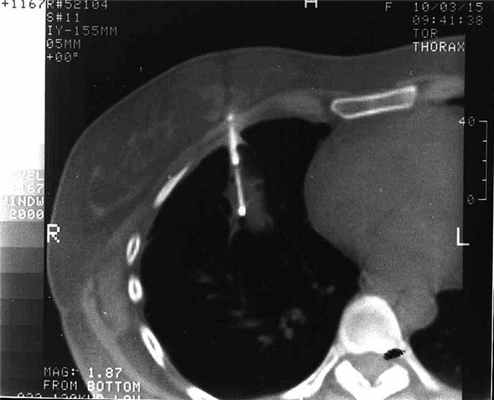

При проведении трансторакальной биопсии легкого получить материал для дальнейшего исследования удалось у 103 пациентов. В 4 наблюдениях проведение пункции оказалось неудачным и морфологический материал не был получен по причине развившегося пневмоторакса (3 наблюдания), не позволившего локализовать иглу в опухоли, и в связи с плотной консистенцией опухоли и ее малым размером (1). Процедура пункции вместе с предварительной КТ-разметкой занимала от 15 до 35 мин. Как правило, для локализации иглы в опухоли было достаточно одного прокола грудной стенки (рис. 2), Рисунок 2. Компьютерная томограмма больного С. Конец иглы локализован в центре опухоли правого легкого. в редких наблюдениях эта процедура осуществлялась повторно.

Трепанационная биопсия была выполнена 69 больным (рис. 3). Рисунок 3. Компьютерная томограмма больной С. На срезе видны две части иглы: троакар у переднего полюса опухоли и проведенный через него стилет с расщепленным концом в центре опухоли. Окончательный диагноз в 57 наблюдениях был представлен злокачественными опухолями. В 53 из них по результатам морфологического исследования правильно верифицировано заболевание (в 83,9% - гистологически, в 76,8% - цитологически). Чувствительность трепанационной биопсии для верификации злокачественного процесса составила 93%. Из 13 больных с неопухолевыми образованиями легких у 12 правильно верифицирован диагноз. Таким образом, точность трепанационной биопсии составила 94,2%. Осложнения наблюдались у 10 (14,5%) больных: пневмоторакс - у 8, кровохарканье - у 2. Клинически значимые осложнения, потребовавшие вмешательства и медикаментозной коррекции, развились в 2 наблюдениях (дренирование плевральной полости, гемостатическая терапия). Отмечено, что при проведении трепанационной биопсии осложнения были более тяжелыми, это вполне соответствует данным литературы, свидетельствующим об увеличении частоты пневмотораксов при использовании игл большего диаметра [3, 8]. По полученному гистологическому материалу 5 больным раком легкого выполнено исследование опухоли на наличие мутации EGFR, что в значительной степени повлияло на тактику лечения.